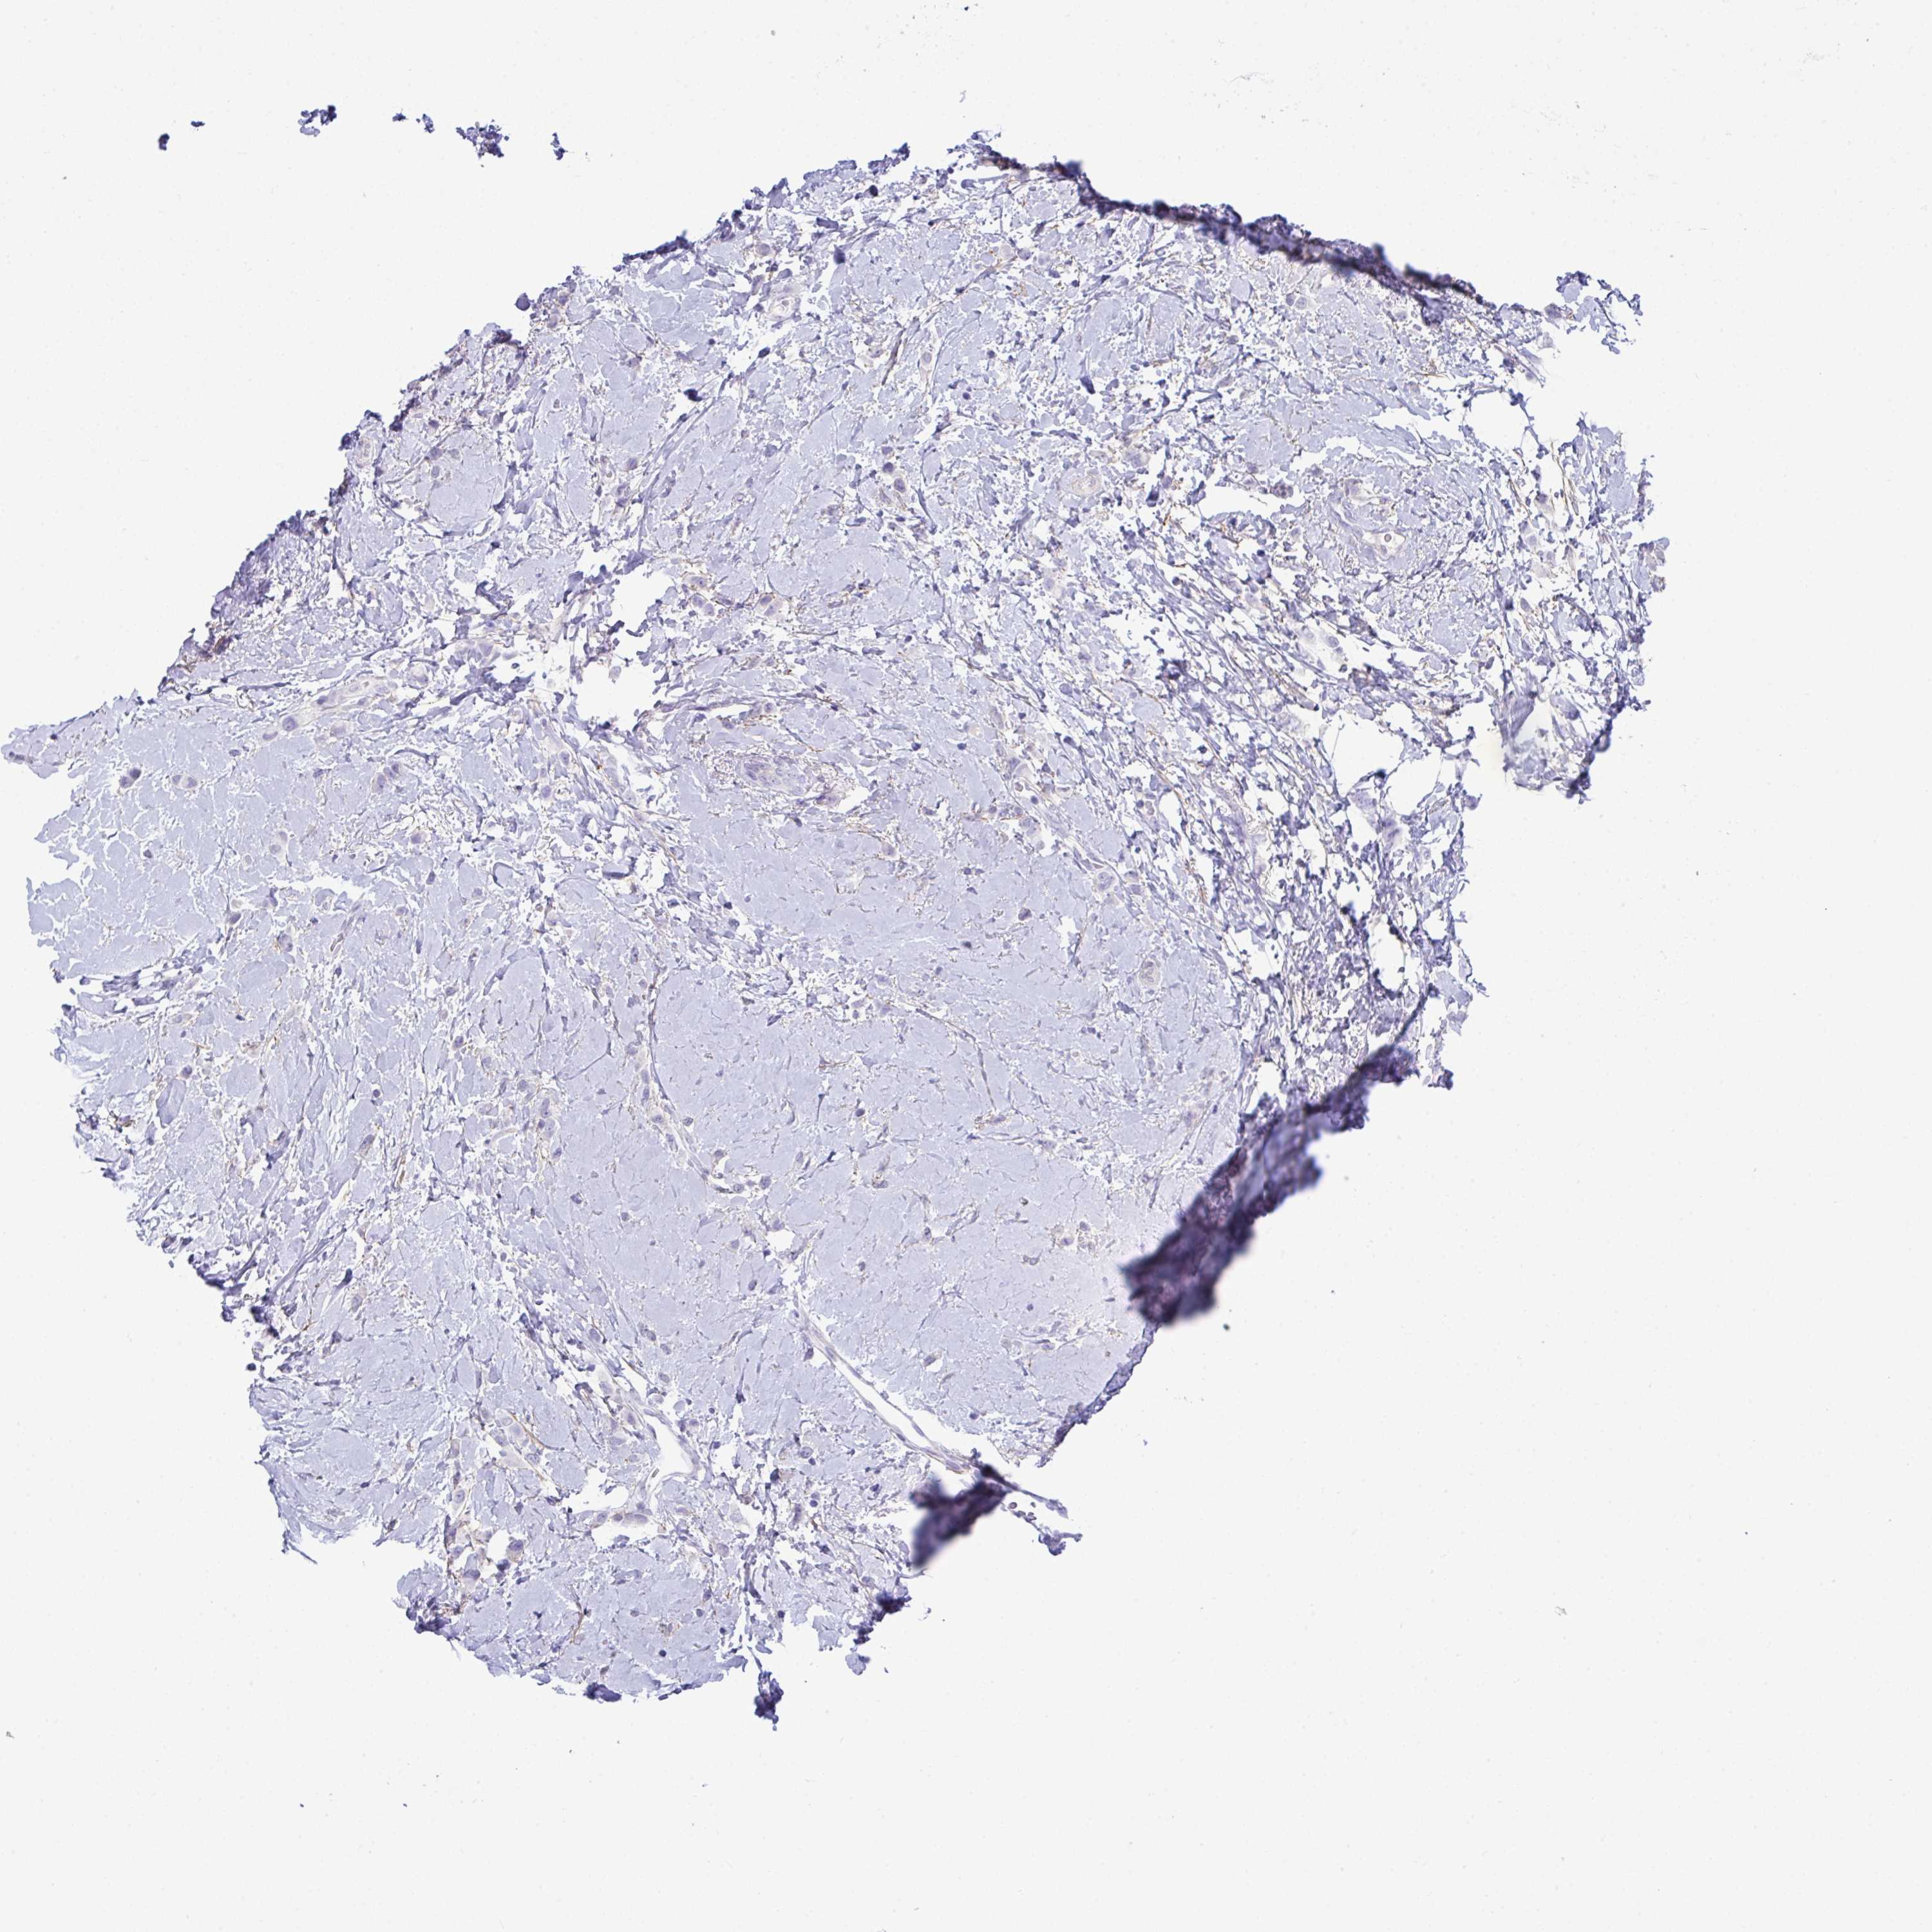

CANCER BREAST CANCER Show tissue menu

BRCA TCGA BRCA VALIDATION PROTEIN EXPRESSION

Breast cancer

Human cancer